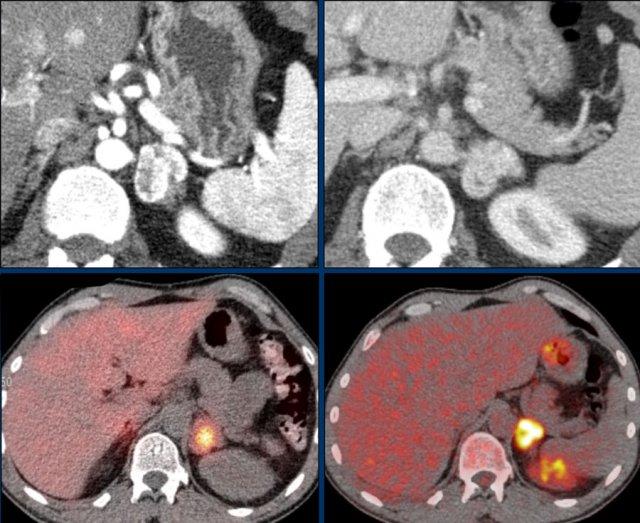

Bệnh nhân này biểu hiện bệnh di căn lan rộng đến phổi, gan và các hạch bạch huyết sau phúc mạc sau khi phẫu thuật cắt bỏ u tủy thượng thận.

Tiếp tục xem PET-CT…

PET-CT của cùng bệnh nhân với DOTATOC gắn nhãn 68 gallium.